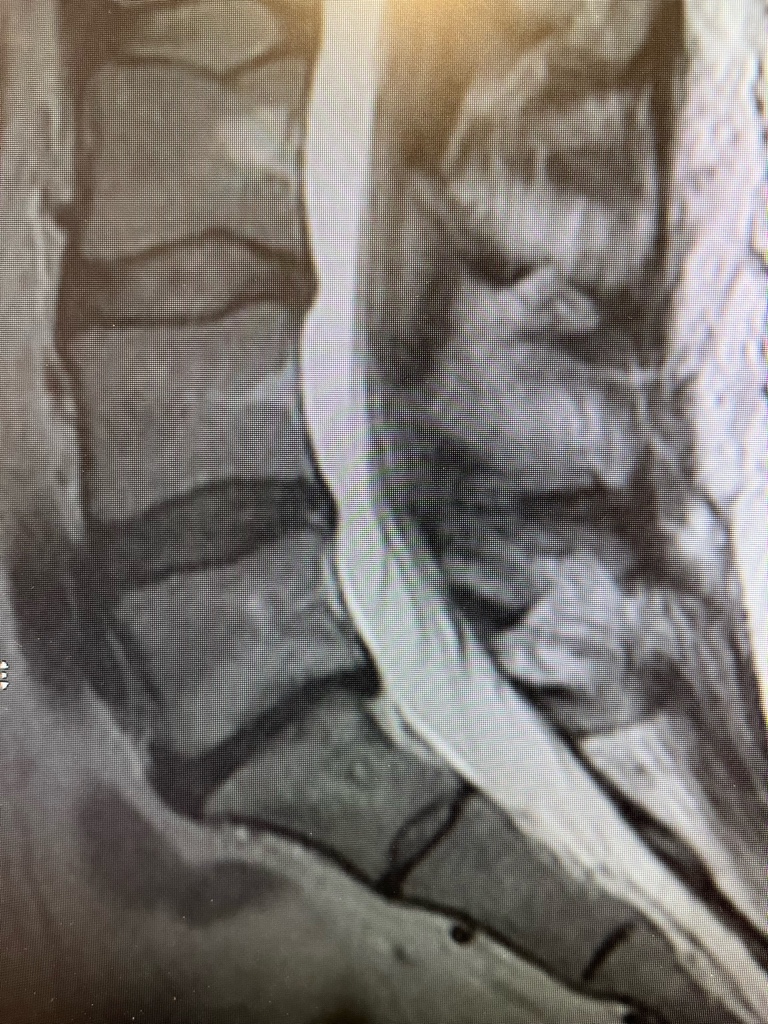

I had an Intracept case at L5 and S1 about 2 months ago - patient reported about 60% improvement, but we got a follow up MRI to evaluate for any other interval changes. There are clear S1 lesions but nothing at L5, any insight into this? We did a 15 minute lesion at S1 and a 7 minute lesion at L5 but I would imagine that shouldn't change post procedural lesion imaging. I'm asking the reps to see if they can get a lesion history from their generator, but L5 was the second lesion we did so I'm 100% certain we watched that count down.

IMG_1159.jpg

IMG_1158.jpg

Thoughts?

There is a lesion at L5 (circled) but the 15 versus 7 definitely look different on mri, not just in size from the cases I’ve seen. 15 looks like a dead zone/void, as in your S1. no idea how the different look impacts the killing of nerve besides trusting Relievant. That said, no drop off in my success rate using primarily seven.

S1 lesion is also low of target. See marked up image. “May” have gotten bvn at the periphery of it. Sometimes the BVN is less than 40% from endplate. Need to review mri pre-op for S1 bvn exact location.

L5 marrow probably just healed faster. I see what looks to be a small residual lesion. How do the T1 sag and ax look? T1 seems to be the most sensitive when I look at lesions.

Hey yeah actually found a small dark lesion on the T1 weighted images. thanks for that!

The lesions also fade I think. I had a hard time seeing lesions on a patient that was ablated a couple years ago.